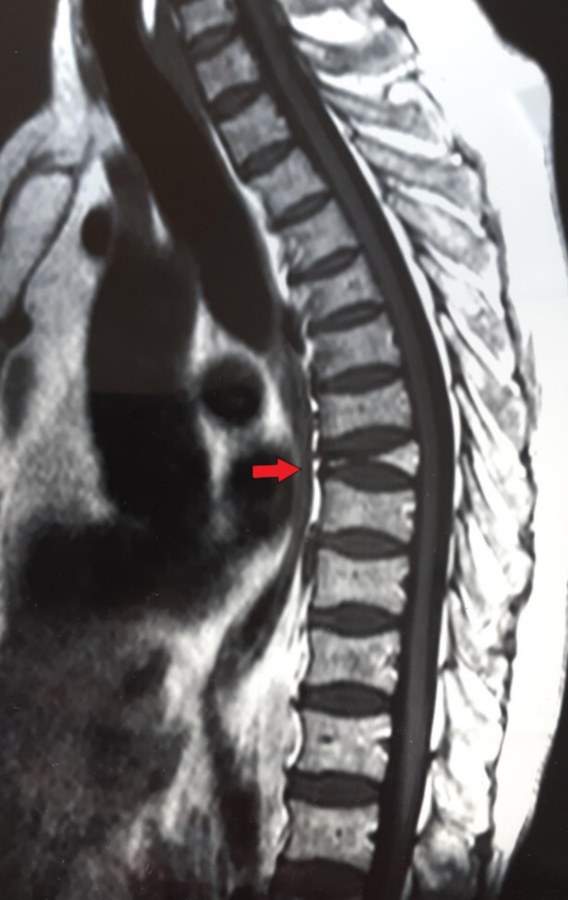

Posteriormente, y como resultado de la toma de radiografías y tomografías, se identificaron marcadores de cambios degenerativos en las articulaciones. Para la columna vertebral se detectó la presencia de lesiones osteoartríticas que incluyen osteofitosis y espondilosis en algunas vertebras torácicas, lumbares y el sacro. Asimismo, se observó en algunos cuerpos vertebrales torácicos signos de osteoporosis (pérdida de densidad ósea) y adelgazamiento derivado en acuñamiento, así como una platispondilia traumática de la vértebra D8 (Fig. 7). Dentro del hueso esponjoso del cuerpo de la octava vértebra torácica, se detectó la presencia de un foco de crecimiento de hueso compacto maduro de pocos centímetros conocido como enostosis (Mann y Hunt, 2005; Fig. 8).

En relación a estas últimas patologías, se solicitó a la Secretaría actuante la entrega de estudios médicos antemortem. Como resultado de dicha diligencia, se pudo contar con una resonancia nuclear magnética que muestra aplastamiento vertebral por fractura patológica a nivel de la octava vértebra torácica. Además de esto, se realizó un centellograma óseo que mostró a nivel de la D8 hipercaptación del material radioactivo, a partir del cual se orientó la investigación a una identificación tentativa (Fig. 9).